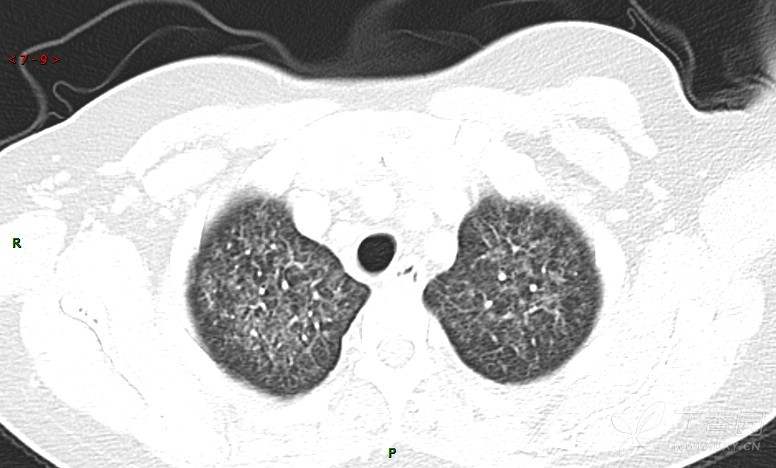

肺内弥漫性网状结节影,PET-CT却无阳性病灶,这是?(附其他2例链接)

女性,58岁,阵发性咳嗽2月,加重1月。

糖类抗原15-3 70.7 U/ml ↑ 0--31.3

癌胚抗原 57.12 ng/mL ↑ 0--5

糖抗原125 166.8 U/ml ↑ 0--35

细胞角蛋白19片段测定 8.32 ng/ml ↑ ≤3.3

糖抗原199 901.79 U/ml ↑ 0--37

患者活检肺组织后行PET/CT检查